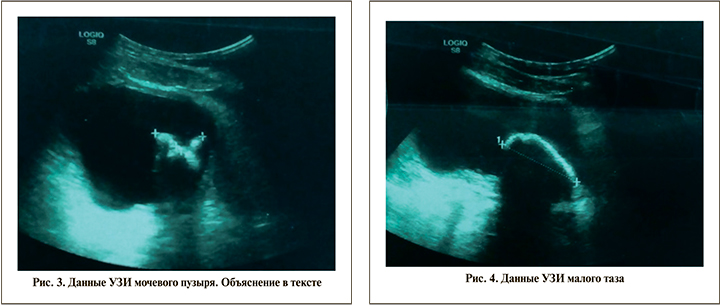

Ультразвуковое исследование (УЗИ) почек, мочевого пузыря, малого таза и органов брюшной полости (рис. 3, 4): в полости мочевого пузыря лоцируется малоподвижная сложной крестообразной конфигурации гиперэхогенная структура, наибольшим размером 45 мм, с акустической тенью (инородное тело металлической плотности с образованием конкремента на нем). Стенка мочевого пузыря в этой зоне деформирована, утолщена. Почки и мочеточники без патологии. При интравагинальном УЗИ: яичники и матка без патологии, ВМК в полости и стенке матки нет (он находится в мочевом пузыре и частично в брюшной полости). Цистоскопия: диффузная гиперемия слизистой мочевого пузыря. Виден крупный камень, фиксированный к задней стенке мочевого пузыря. При смещении камня клювом цистоскопа видно, что конкремент сформирован на ВМК, который перфорировал пузырную стенку. Диагноз: инородное тело (ВМК), расположенное в мочевом пузыре и частично в брюшной полости. Осложнения: перфорация стенки мочевого пузыря, вторичный камень мочевого пузыря, хронический цистит.